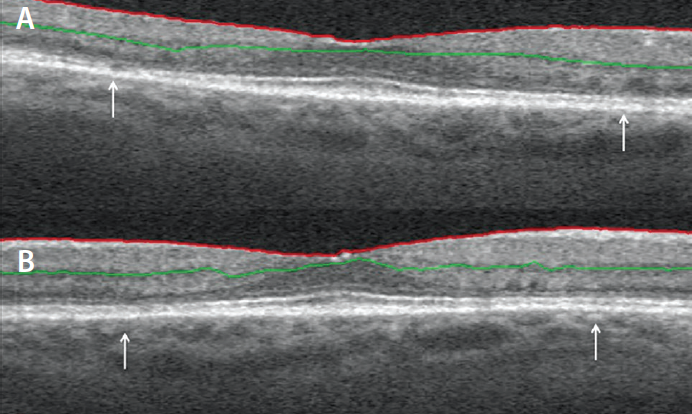

Figure 3. SD-OCT scan of the right eye in a patient with hydroxychloroquine toxicity is shown. Arrows indicate areas of outer retinal thinning on vertical (A) and horizontal B-scan (B).

SD-OCT is a widely available test that can be easily performed with reproducible results, regardless of patient compliance. In analyzing SD-OCT, it is imperative to pay special attention to the outer retina (Figure 3). Thinning of the photoreceptor layer, ellipsoid layer, outer nuclear layer, and RPE can be among the earliest signs of hydroxychloroquine toxicity.4 These changes often occur in the parafoveal area, although they can be more peripheral in Asian patients.